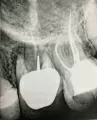

Через 2 недели мне предстоит резекция трех зубов (13,14 и 15) и удаление кисты, в челюстно-лицевой хирургии. Перед резекцией зубы нужно обязательно запломбировать.

Скажите, пожалуйста, есть ли разница, чем пломбировать каналы перед резекцией? И какой материал лучше?